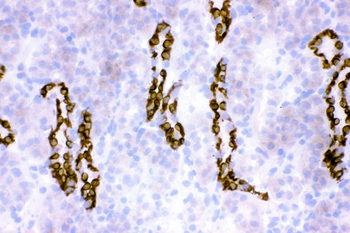

10 μg, 100 μg - Anti-S100 alpha 6/S100A6 Antibody [orb315184]

FC, ICC, IF, IHC, WB

Human, Mouse, Rat

Rabbit

Polyclonal

Unconjugated

10 μg, 100 μg - Anti-HSD11B2 Antibody [orb316541]